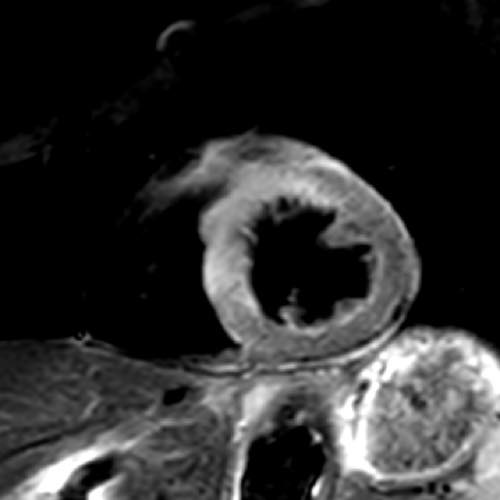

さらに、これまでMRIで評価されてきた心筋性状も、我々の考案する画像処理方法(SMILIE:subtraction myocardial image for late iodine enhancement)によって冠動脈と一緒に評価する事が可能となっています。

通常の遅延相の画像(左)では、心筋の異常を指摘するのは困難です。SMILIE(右)では、心筋梗塞となっている部分(矢印)が明瞭に描出されています。